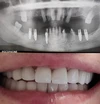

Implant tedavisi